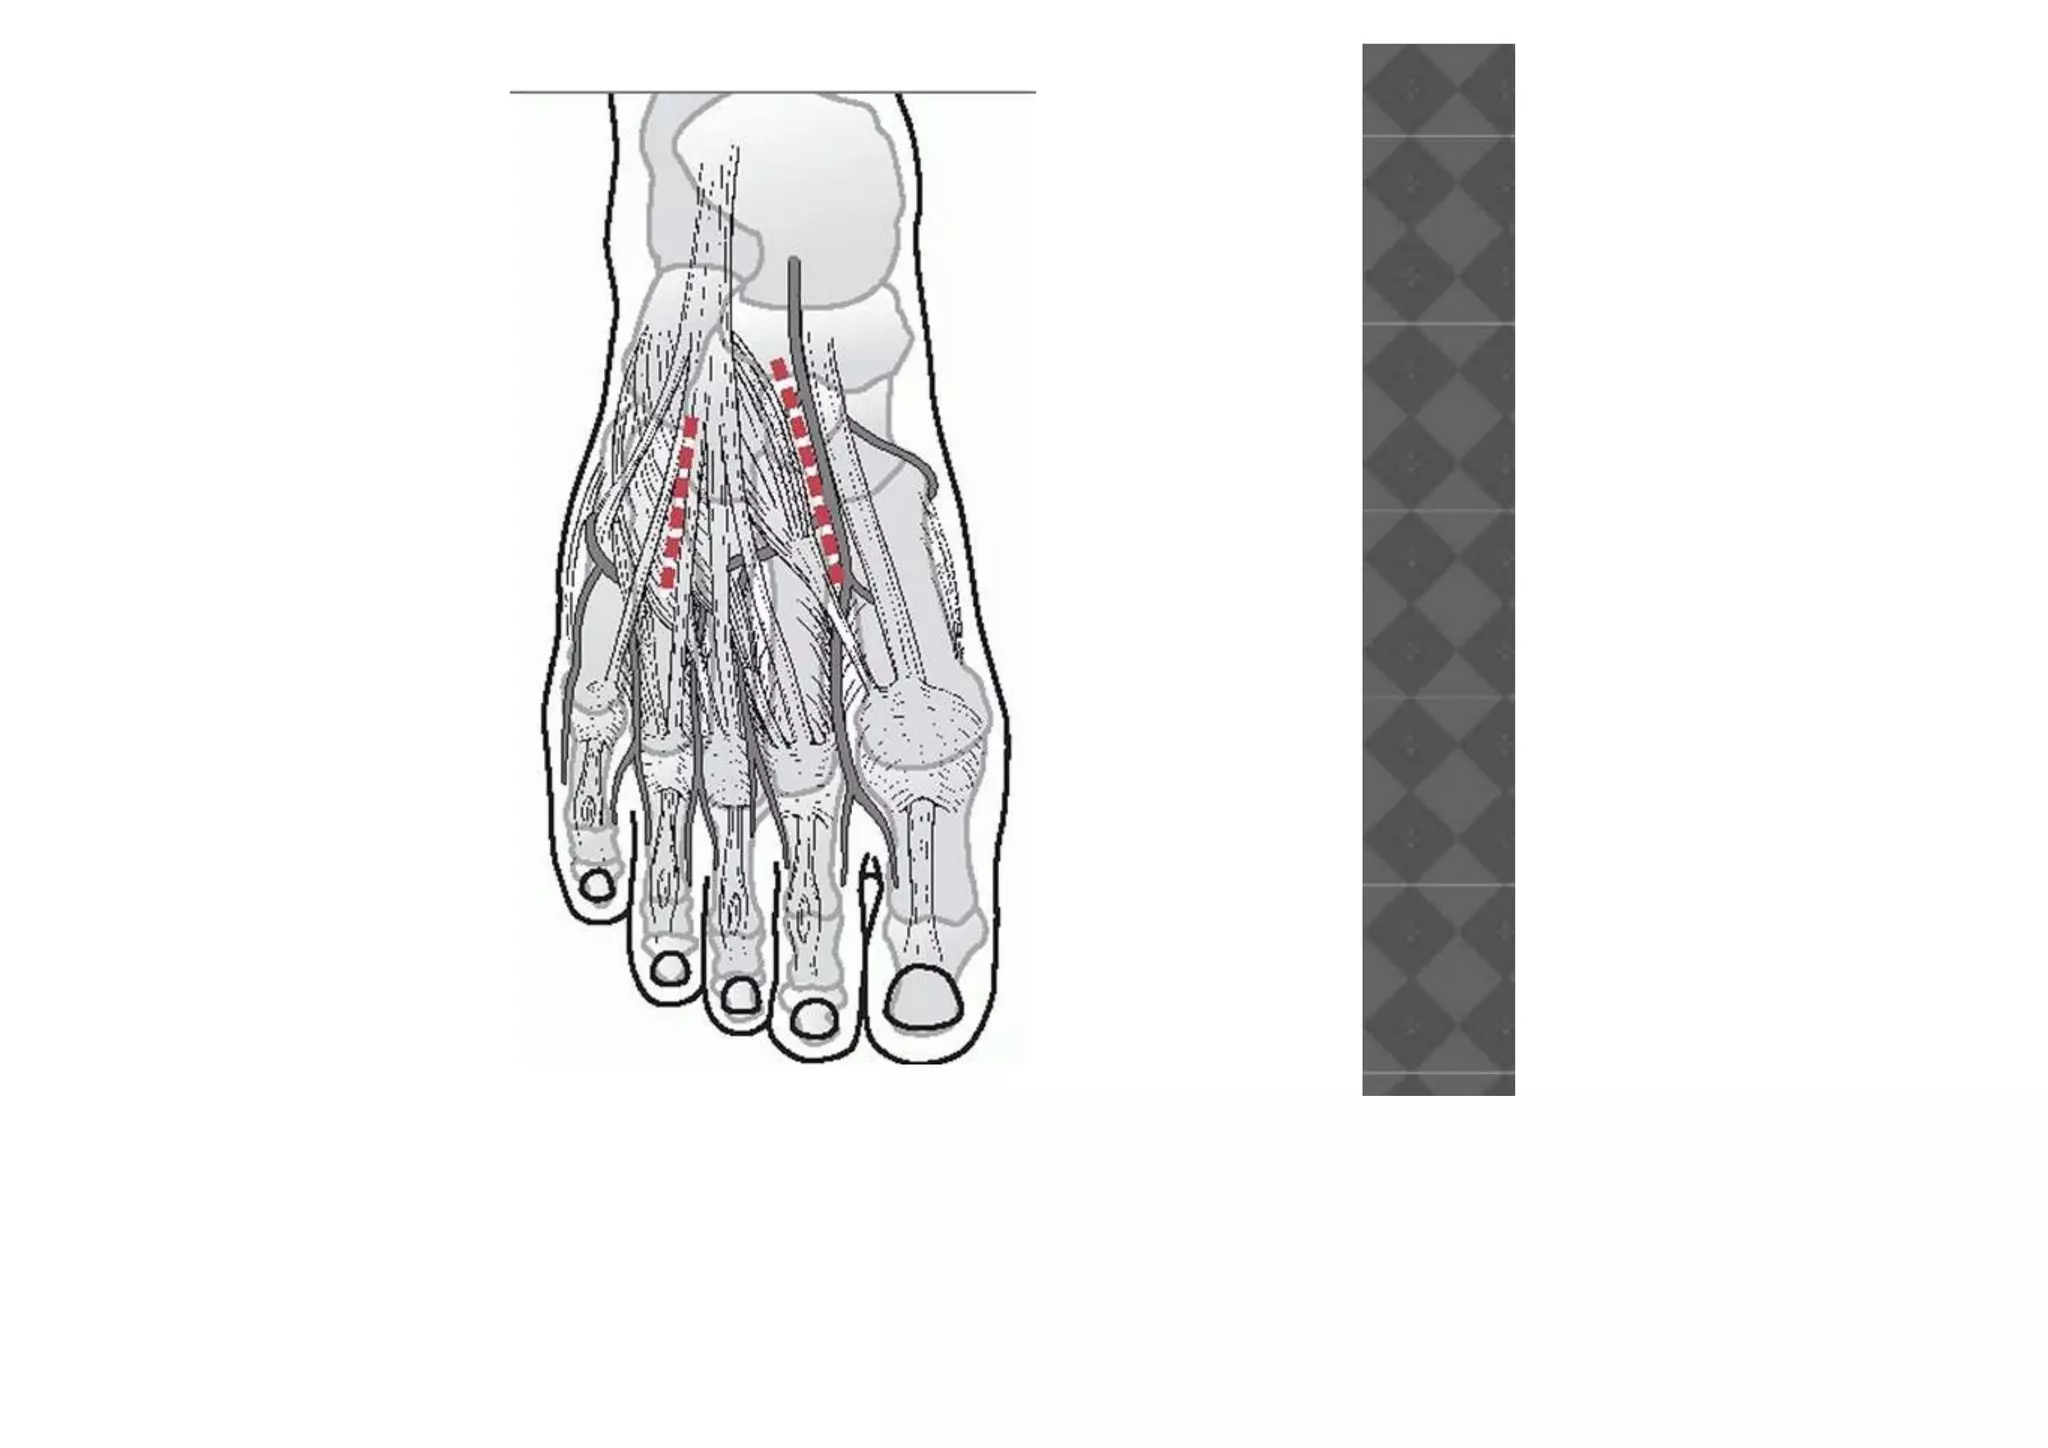

• The most common approach is using two

longitudinal incisions.

• The first is centered over the first/second

intermetatarsal space allowing identification

of the neurovascular bundle and access to

the medial two tarsometatarsal joints.

• A second longitudinal incision is made over

the fourth metatarsal

OPERATIVE MANAGEMENT • Thisshould be considered when displacement of the tarsometatarsal joint is >2 mm. • The best results are obtained through anatomic reduction and stable fixation. • The most common approach is using two longitudinal incisions.

• The firstis centered over the first/second intermetatarsal space allowing identification of the neurovascular bundle and access to the medial two tarsometatarsal joints. • A second longitudinal incision is made over the fourth metatarsal

• #31 ■ With the patient under a regional or general anesthetic, make a dorsal incision lateral to the extensor hallucis longus tendon over the interval between the base of the first and second metatarsals, slightly more lateral if access to the third tarsometatarsal joint is necessary. At the distal extent of the excision, preserve the most medial branch of the dorsal medial cutaneous nerve. ■ A second incision may be needed more laterally if open reduction of the fourth and fifth tarsometatarsal joints is necessary (Fig. 88-66A). ■ Locate and incise the inferior extensor retinaculum

• #32 . ■ Isolate the dorsalis pedis artery and deep peroneal nerve, and use a vessel loop for retraction of these structures medially or laterally to allow inspection of different areas of the Lisfranc joint